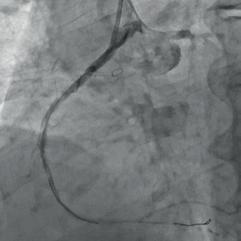

After medical preparation, PCI of the RCA was started. In a standard procedure the RCA was opened and multiple dilatations of the vessel were performed (Fig. 2a). After predilection, a diffusely altered vessel with a sub-occlusive stenosis of the middle RCA was identified. The lesions were sequentially dilated with non-compliant balloons, but a critical, calcified lesion in the middle RCA could not be dilated. The lesion was then attempted to be dilated with an ultra-high pressure balloon (OPN NC 2.5  15 mm Super High Pressure Balloon; SIS Medical AG, Frauenfeld, Switzerland). A slightly undersized OPN balloon was used in relation to the vessel diameter. The OPN balloon was sequentially inflated, resulting in a persistent dog bone appearance at the site of the lesion (Fig. 2b). Finally, at a pressure of 50 at-

Figure 1: Initial appearance of the RCA in the LAO view. Figure 2a: RCA dilatation with

Figure 2b: RCA dilatation with an OPN NC balloon

Figure 2c: Large dissection and vessel occlusion after balloon rupture.